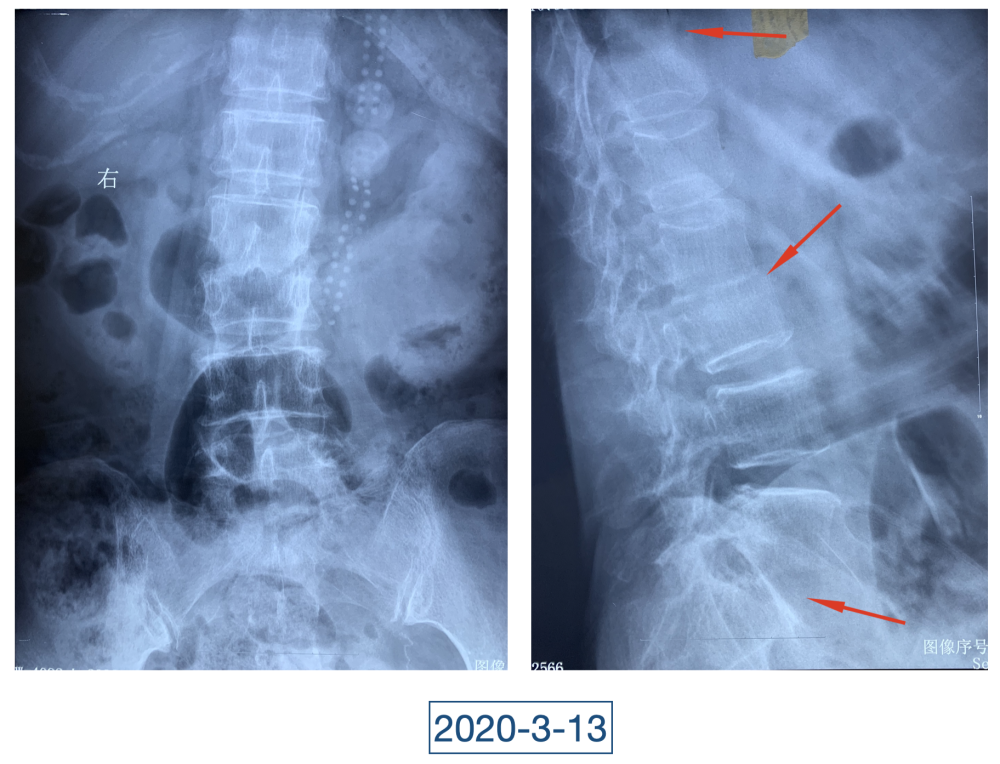

“虽说没到奄奄一息的地步,但一看就是患了大病,整个人都瘦脱相了。”李辉是西安市红会医院关节病医院病区副主任,2020年4月初第一次见到黄大娘时,他吓了一跳。黄大娘今年61岁,2019年腊月二十九,在家打扫卫生准备迎接新年的她突然开始高烧不退,腰背也痛。连夜送到当地医院补液、止疼、退烧、抗感染,一套组合拳下来烧是退了,疼痛的症状却持续在加重。从过年到正月,一直在当地医院输液、打针,黄大娘都没有好转,疼痛的地方反而越来越多。大概过半月,就多一个地方,腰、背、胸、颈部、关节、脚……此起彼伏,全身上下都觉得疼痛无比。哪里疼就去哪个科,今年四月前,黄大娘辗转多家医院多个科室寻求治疗,住院出院了一次又一次,连最高级别的抗生素都用到了,但就是没有效果。

全身上下11处骨关节被破坏!密密麻麻的诊断看得李辉毫无思绪,这么久都查不出来的病因能让他查出来吗?一时间,他也说不出话。看着黄大娘深深凹陷的双眼,浑身上下几乎看不见肉,就像罩着一层饥饿的青黄色的薄皮。过了好一会儿,他叹了口气,说:“先住下吧,用药把关节疼痛缓解一下,再想办法。”

经过科室讨论、会诊,李辉也查阅了很多资料,按照黄大娘的症状,他跟之前的接诊医生一样,觉得应该是骨关节感染。可之前的穿刺、培养各种检查也做过,为什么没有找到致病菌?李辉想,或许是检查中出现了问题,没有查对地方。于是他决定,在B超引导下骨穿刺,通过最新技术精准定位病灶,只有这样也许才能抓到真正的“罪犯”。

在黄大娘入院第四天,李辉将她推入检查室,结果很快出来了,为烟曲霉菌感染。这个结果验证了李辉的想法,也解释了此前抗感染药物为何一直不奏效。“找到元凶就好办了,对症用药就可以。真菌感染本来治疗时间就很长,骨科类感染灶治疗时间更长,用了5个月的时间,终于治好了。”

近日随访得知黄大娘身体好转,李辉脸上的笑容掩饰不住,他说,据查阅文献,11处感染灶,这是全世界感染灶最多的骨关节感染,但现在,这罕见、复杂的病已经被治愈。